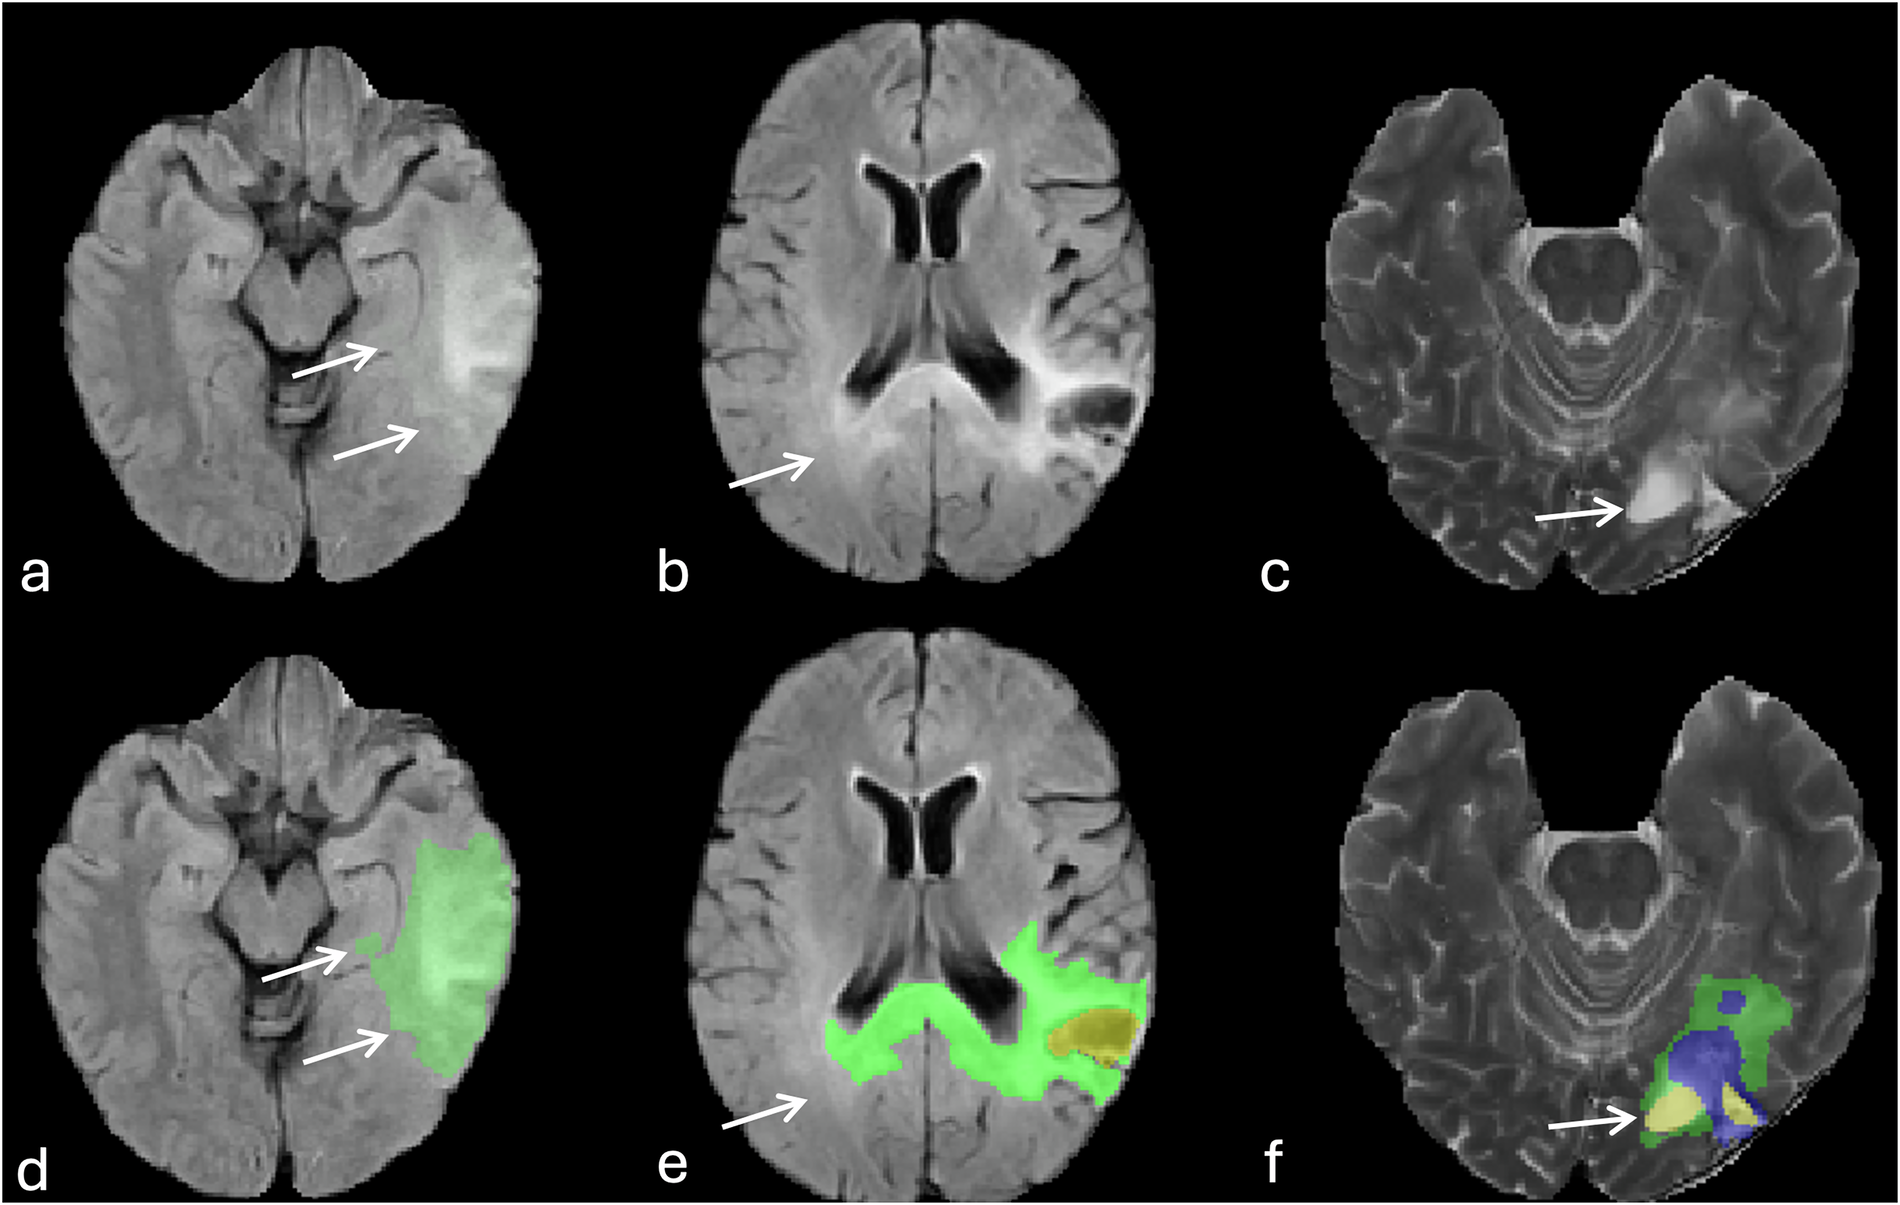

Fig. 7

Errors of automatic tumor segmentation related to T2 and FLAIR signal abnormalities. (a, and d) image show the oversampling of FLAIR hyperintensities surrounding the tumor (arrows). (b, and e) images show incomplete delineation of FLAIR hyperintensities particularly in the contralateral occipital lobe (arrows). (c, and f) images represent misidentification of ventricular zone (occipital horn of the left lateral ventricle, arrows) adjacent to the tumor an assigning it as part of the resection cavity (yellow).